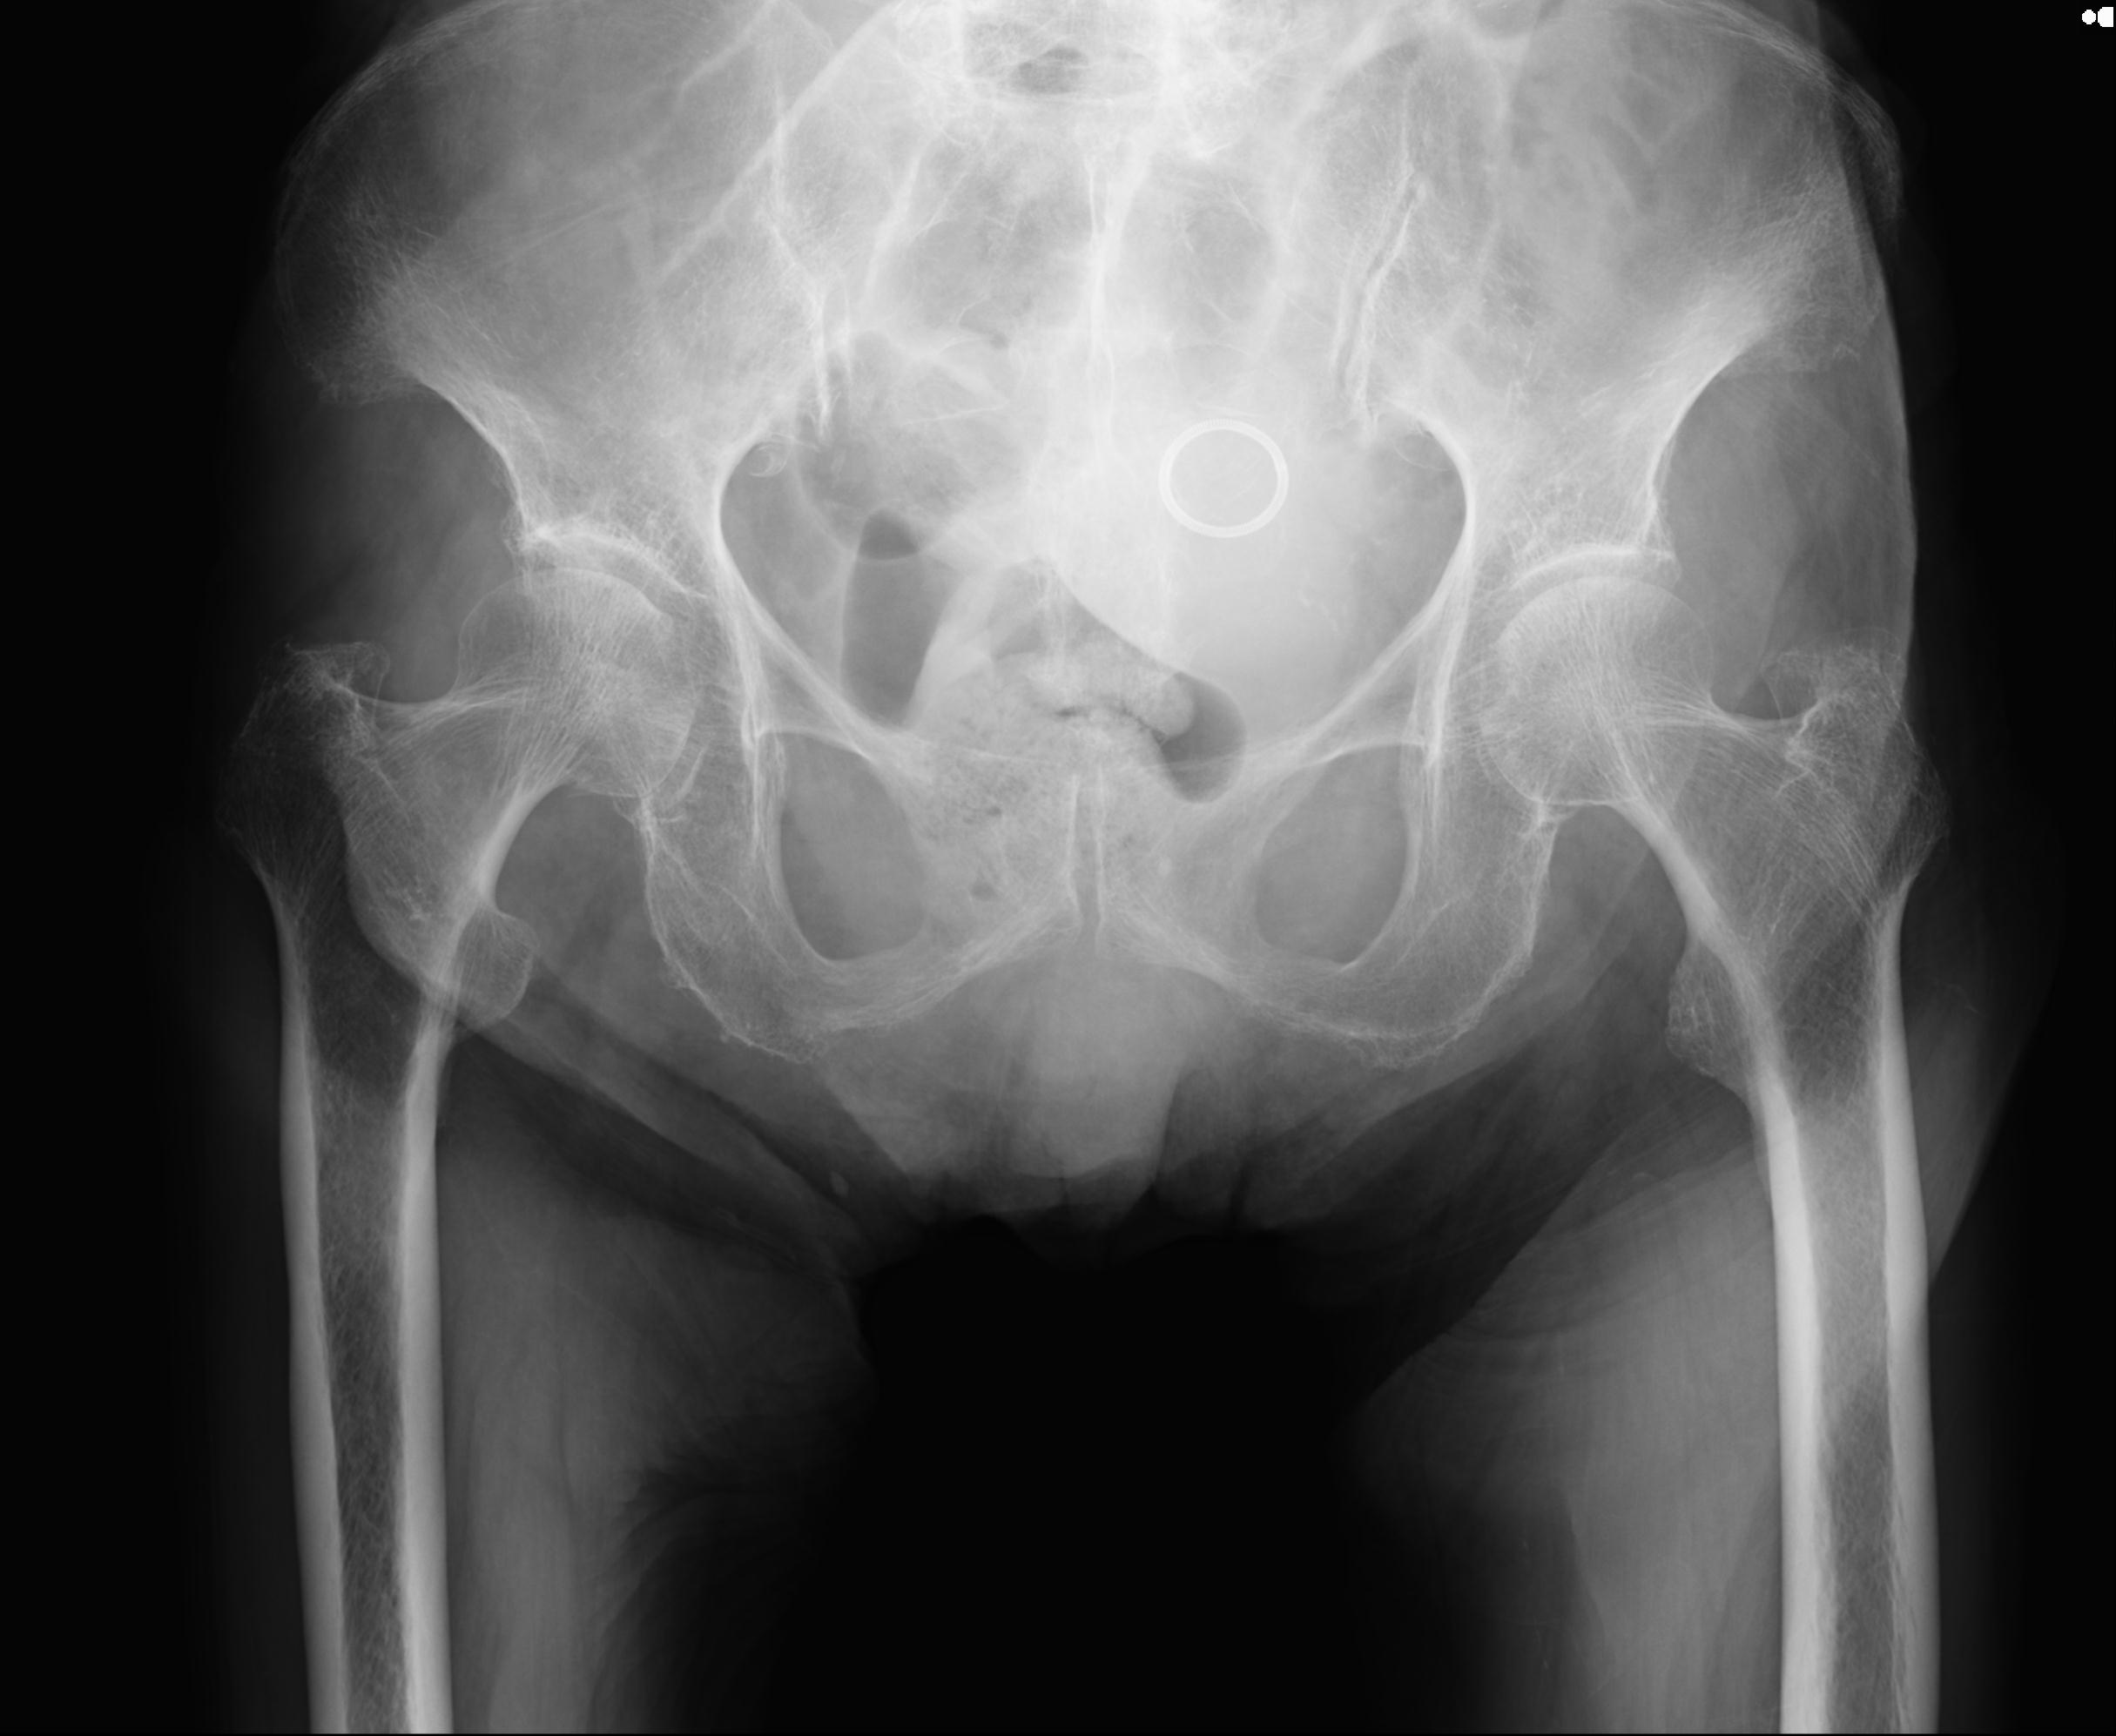

100703 1/27 両股正面+軸 1/29 両股正面+軸 94歳女性 パンソンロン

46666 1/28 両股正面+軸と 1/26 右手関節 2R 76歳女性 右転子部骨折

37 1/18 両股正面+軸 1/22 2R 86歳女性 右転子下